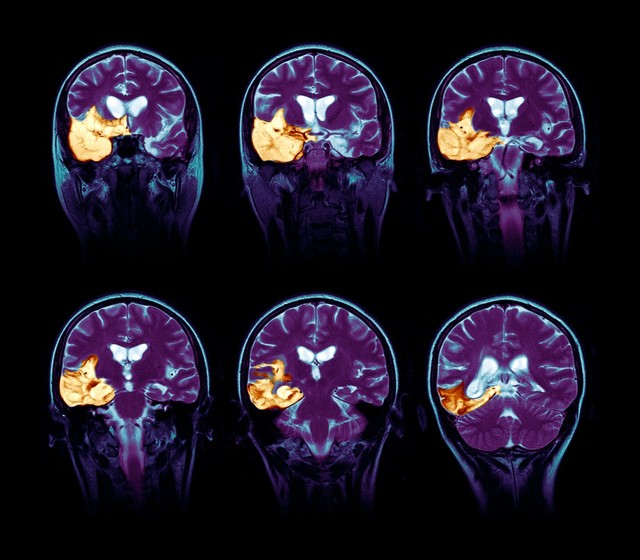

Godina 2019. svakako je bila godina u kojoj su planirali svadbu. Međutim, u toj godini bilo je i nekih ne samo neplaniranih, već i teških dana. Nikola, Sarin voljeni muž, 2. marta te 2019. dobio je dijagnozu. Nakon mesec dana glavobolja, nešto jačih nego inače, i bola u očima, koje su pripisali umoru i napornom radu, snimak magnetne rezonance pokazao je tumor na mozgu.

– Tačno smo znali. Imao je i neke propratne simptome, kod njega je to bila štucavica. Radili smo magnetnu. Pokazala je da se tumor proširio – kazala je za Telegraf.rs navodeći da se u vanrednom stanju produžio termin za snimanje magnetnom rezonancom, te da ih je snimak iz juna neprijatno iznenadio: – Trebalo je da se uradi nova magnetna, da se vidi kako dalje, međutim, njemu se toliko pogoršalo stanje da mi više nismo čekali, nego smo prešli u inostranstvo na lečenje.

Ističe da je Nikolino stanje sada bolje, te da su to pokazala dva snimka magnetne rezonance posle lečenja u Turskoj.